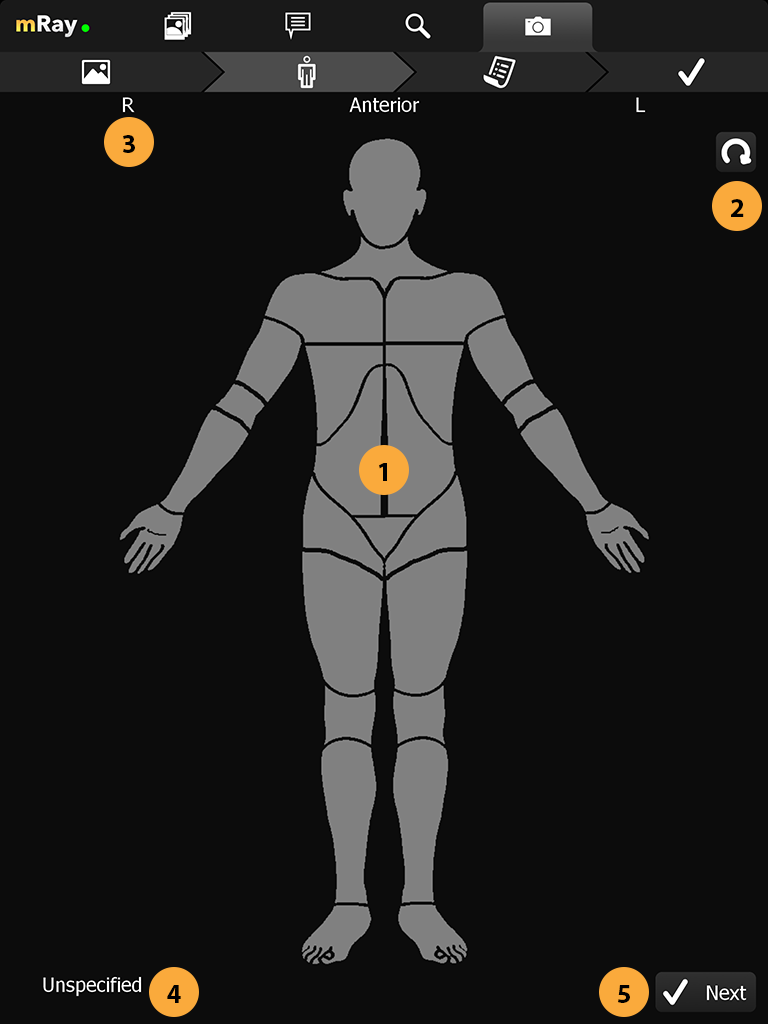

Neue Merkmale über Fotodokumentation Kamera hinzugefügt.

Aufnahme von Bildern zur Wunddokumentation. Versand der Aufnahme als DICOM Datei an ein PACS inkl. aller notwendigen Meta-Informationen